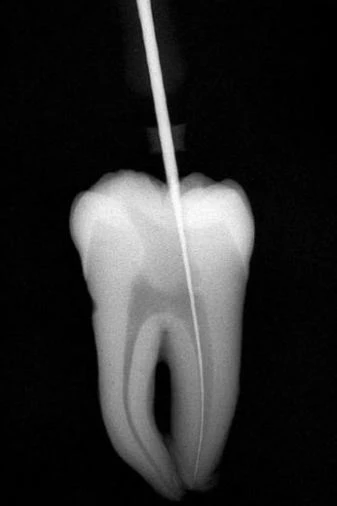

Những vùng cong này cần được loại trừ trước bằng phương pháp “kháng độ cong” của Abou-Rass, Frank, và Glick như đã nói trên. Nếu xoang tủy giúp dụng cụ sửa soạn ống tủy có thể vào thẳng đến 1/3 chóp thì vật liệu và dụng cụ trám bít cũng vào được (hình 11.9).

Hình 11.9. Xoang tủy được làm đúng cho phép đi thẳng vào 1/3 chóp chân răng, thậm chí cả dụng cụ trám ống tủy cũng vào được